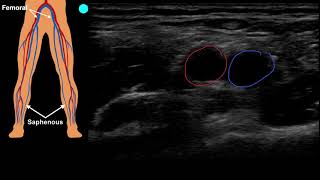

POCUS - Right Lower Extremity Deep Venous Thrombosis (DVT)

Ecografía clínica de extremidades inferiores - Evaluación de TVP - Algoritmo para el paciente de ...

Ecografía clínica - Trombosis venosa profunda (TVP) de las extremidades inferiores - Actualizada

Cómo realizar ecografías venosas de extremidades inferiores + Consejos para pacientes con dificul...